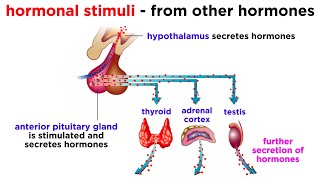

The Endocrine System Endocrine Organs - BEST Way to Learn All the Endocrine Organs and What They Do

Endocrine Organs - BEST Way to Learn All the Endocrine Organs and What They Do Endocrine Glands & Functions | Parathyroidism Nursing | Made Easy NCLEX

The Endocrine System Endocrine Organs - BEST Way to Learn All the Endocrine Organs and What They Do

Endocrine Organs - BEST Way to Learn All the Endocrine Organs and What They Do Endocrine Glands & Functions | Parathyroidism Nursing | Made Easy NCLEX